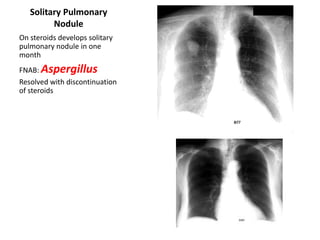

Solitary Pulmonary

Nodule

On steroids develops solitary

pulmonary nodule in one

month

FNAB: Aspergillus

Resolved with discontinuation

of steroids